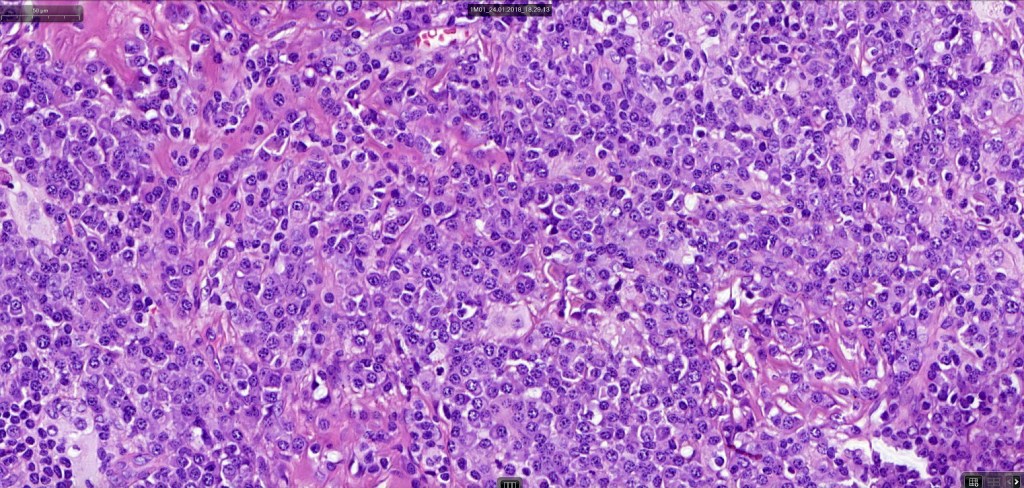

•Histiocytes are large with irregular borders and abundant cytoplasm

• Vesicular nuclei with a prominent nucleoli

•Emperipolesis of lymphocytes, plasma cells & neutrophils

•Background population of lymphocytes, plasma cells, neutrophils, eosinophils & variable numbers of xanthoma cells